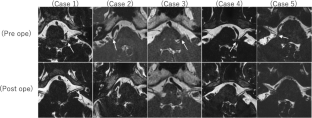

Hemifacial spasm (HFS) is often caused by compression of the vertebral artery (VA) directly or indirectly as a result of other intervening vessels, so VA-associated HFS is difficult to treat. Recently, we have achieved good surgical outcomes using a far lateral approach and temporary clamping of V3 for VA-associated HFS. Herein, we present our method with an accompanying surgical video. From April 2018 to March 2019, 5 patients with VA-associated HFS underwent surgery, and pre-and postoperative symptoms and postoperative complications were evaluated. In the procedure, the suboccipital muscles were dissected and reflected layer by layer, and the extracranial VA (V3) was secured within the suboccipital triangle. A lateral suboccipital craniotomy followed by far lateral drilling was made to widen the surgical field from the caudolateral side. After reducing the VA flow pressure by temporary clamping of V3, the VA was transposed using a Teflon sling via two triangular space above and below the lower cranial nerves (LCNs). Causative vessels included direct VA compression in two cases and intervening vessels in three cases. The symptoms disappeared in four cases and improved satisfactorily in one case. One patient had mild hearing loss (approximately 10 dB) and hoarseness, but both improved 9 months after surgery. There was no postoperative cerebrospinal fluid leakage in any cases. A wide surgical field via the far lateral approach and the temporary clamping of V3 contributed to thorough observation of the REZ and safe and complete VA transposition.